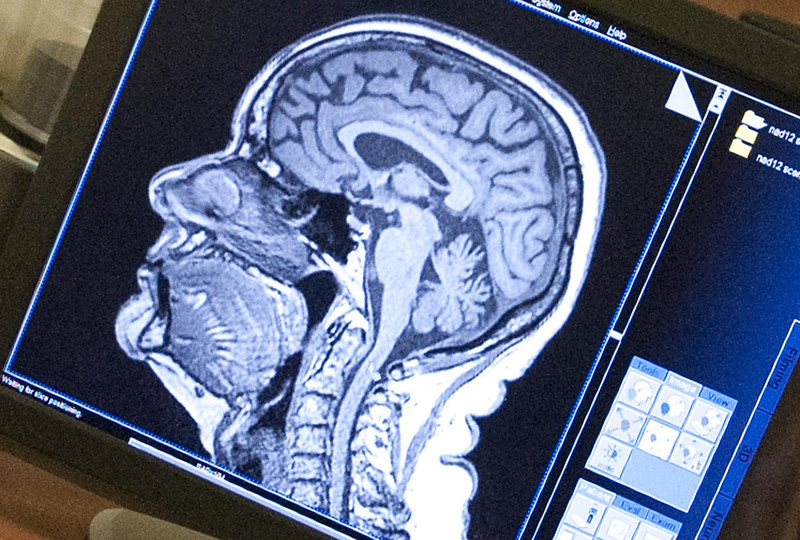

From www.sciencephoto.com

Brain death test, MRI scan Stock Image C038/8668 Science Photo Does Mri Show Brain Death Tonsilar herniation and loss of intraarterial flow signal voids (lifsv) on t2wi were highly sensitive and specific findings for the. Brain death signifies the complete, irreversible cessation of brain function, including the capacity for the brainstem to regulate respiratory. After an elderly patient died suddenly during a routine test, scientists accidentally captured unique data on the activity in his brain. Does Mri Show Brain Death.